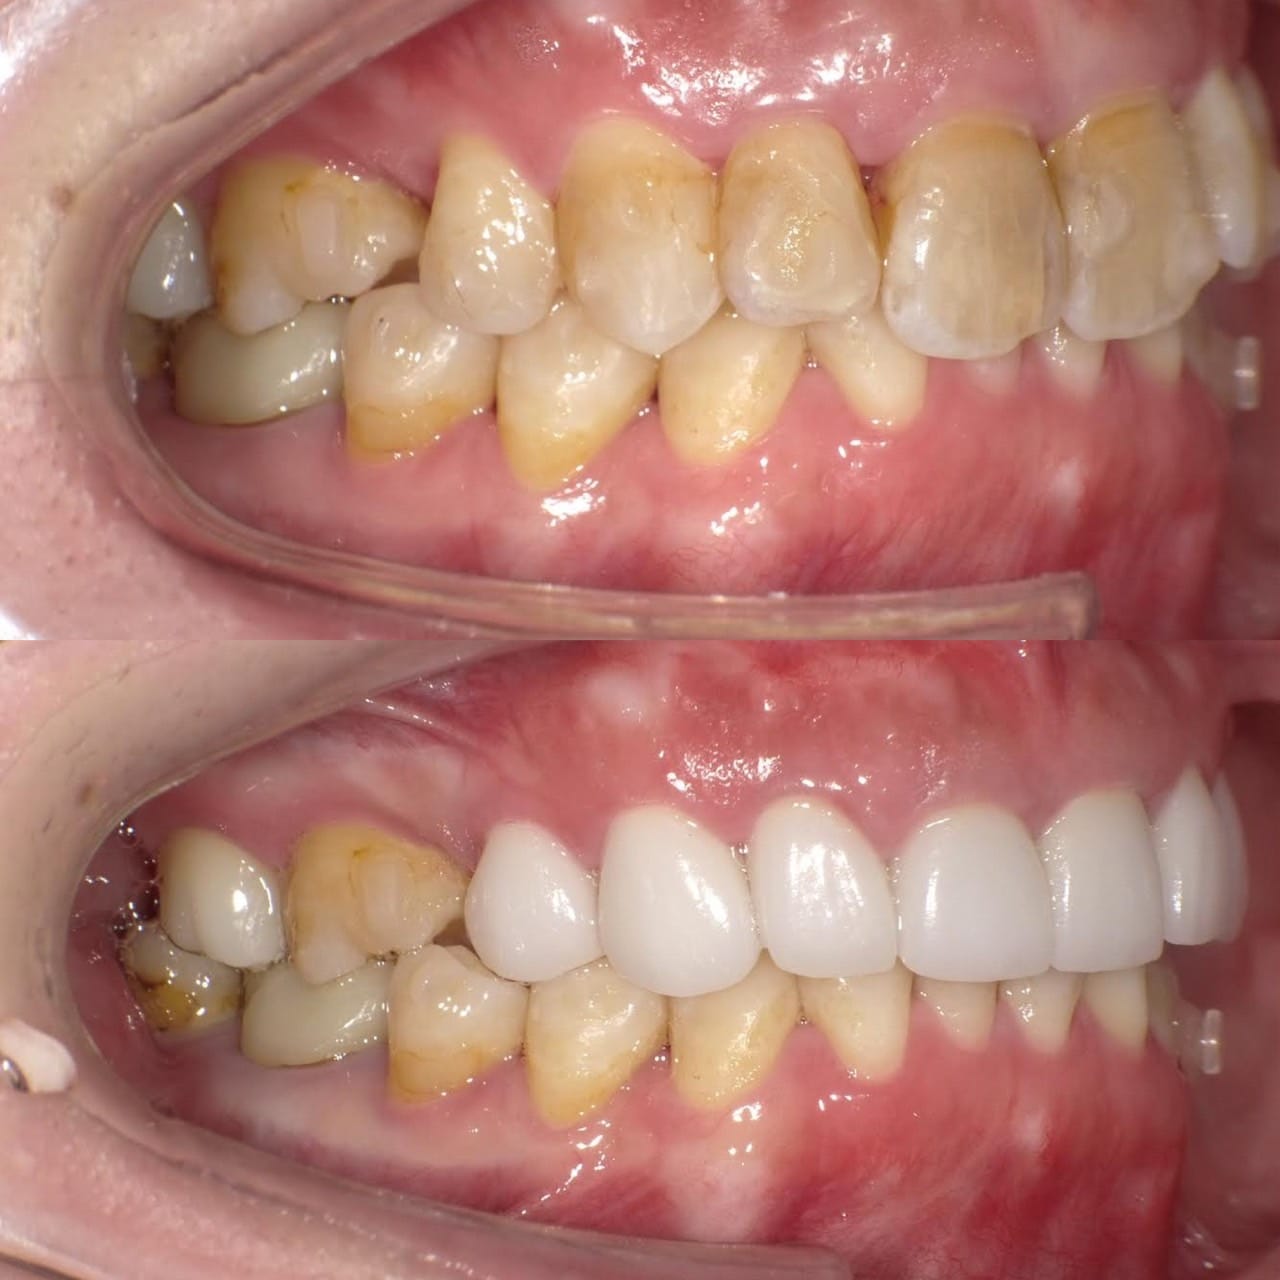

Case016 – インプラント

噛み合わせから審美的なところまで、トータルで治療させて頂いた患者様です。

ここまでやるとなると、できないクリニックもありますし、できるところでも年単位でかかってしまうクリニックが大半だと思いますが、今回は4月末にカウンセリングでご来院いただき、5月に治療をスタートして9月末には診療が終わっています。

治療回数や、治療期間がかかってしまうと、患者様も通院が辛くなったり疲れてしまったりしてしまうと思います。どんどん綺麗になっていく、食事がしやすくなっていくという実感がある方が患者様に楽しく治療に臨んでいただけると思うので、私は診療のスピード感を大切にしています。

トータルでやらせていただいたので、噛み合わせなどの機能面から外見などの審美性もかなり良くなり、患者様にも満足して頂けてよかったです。

治療期間 約4ヶ月